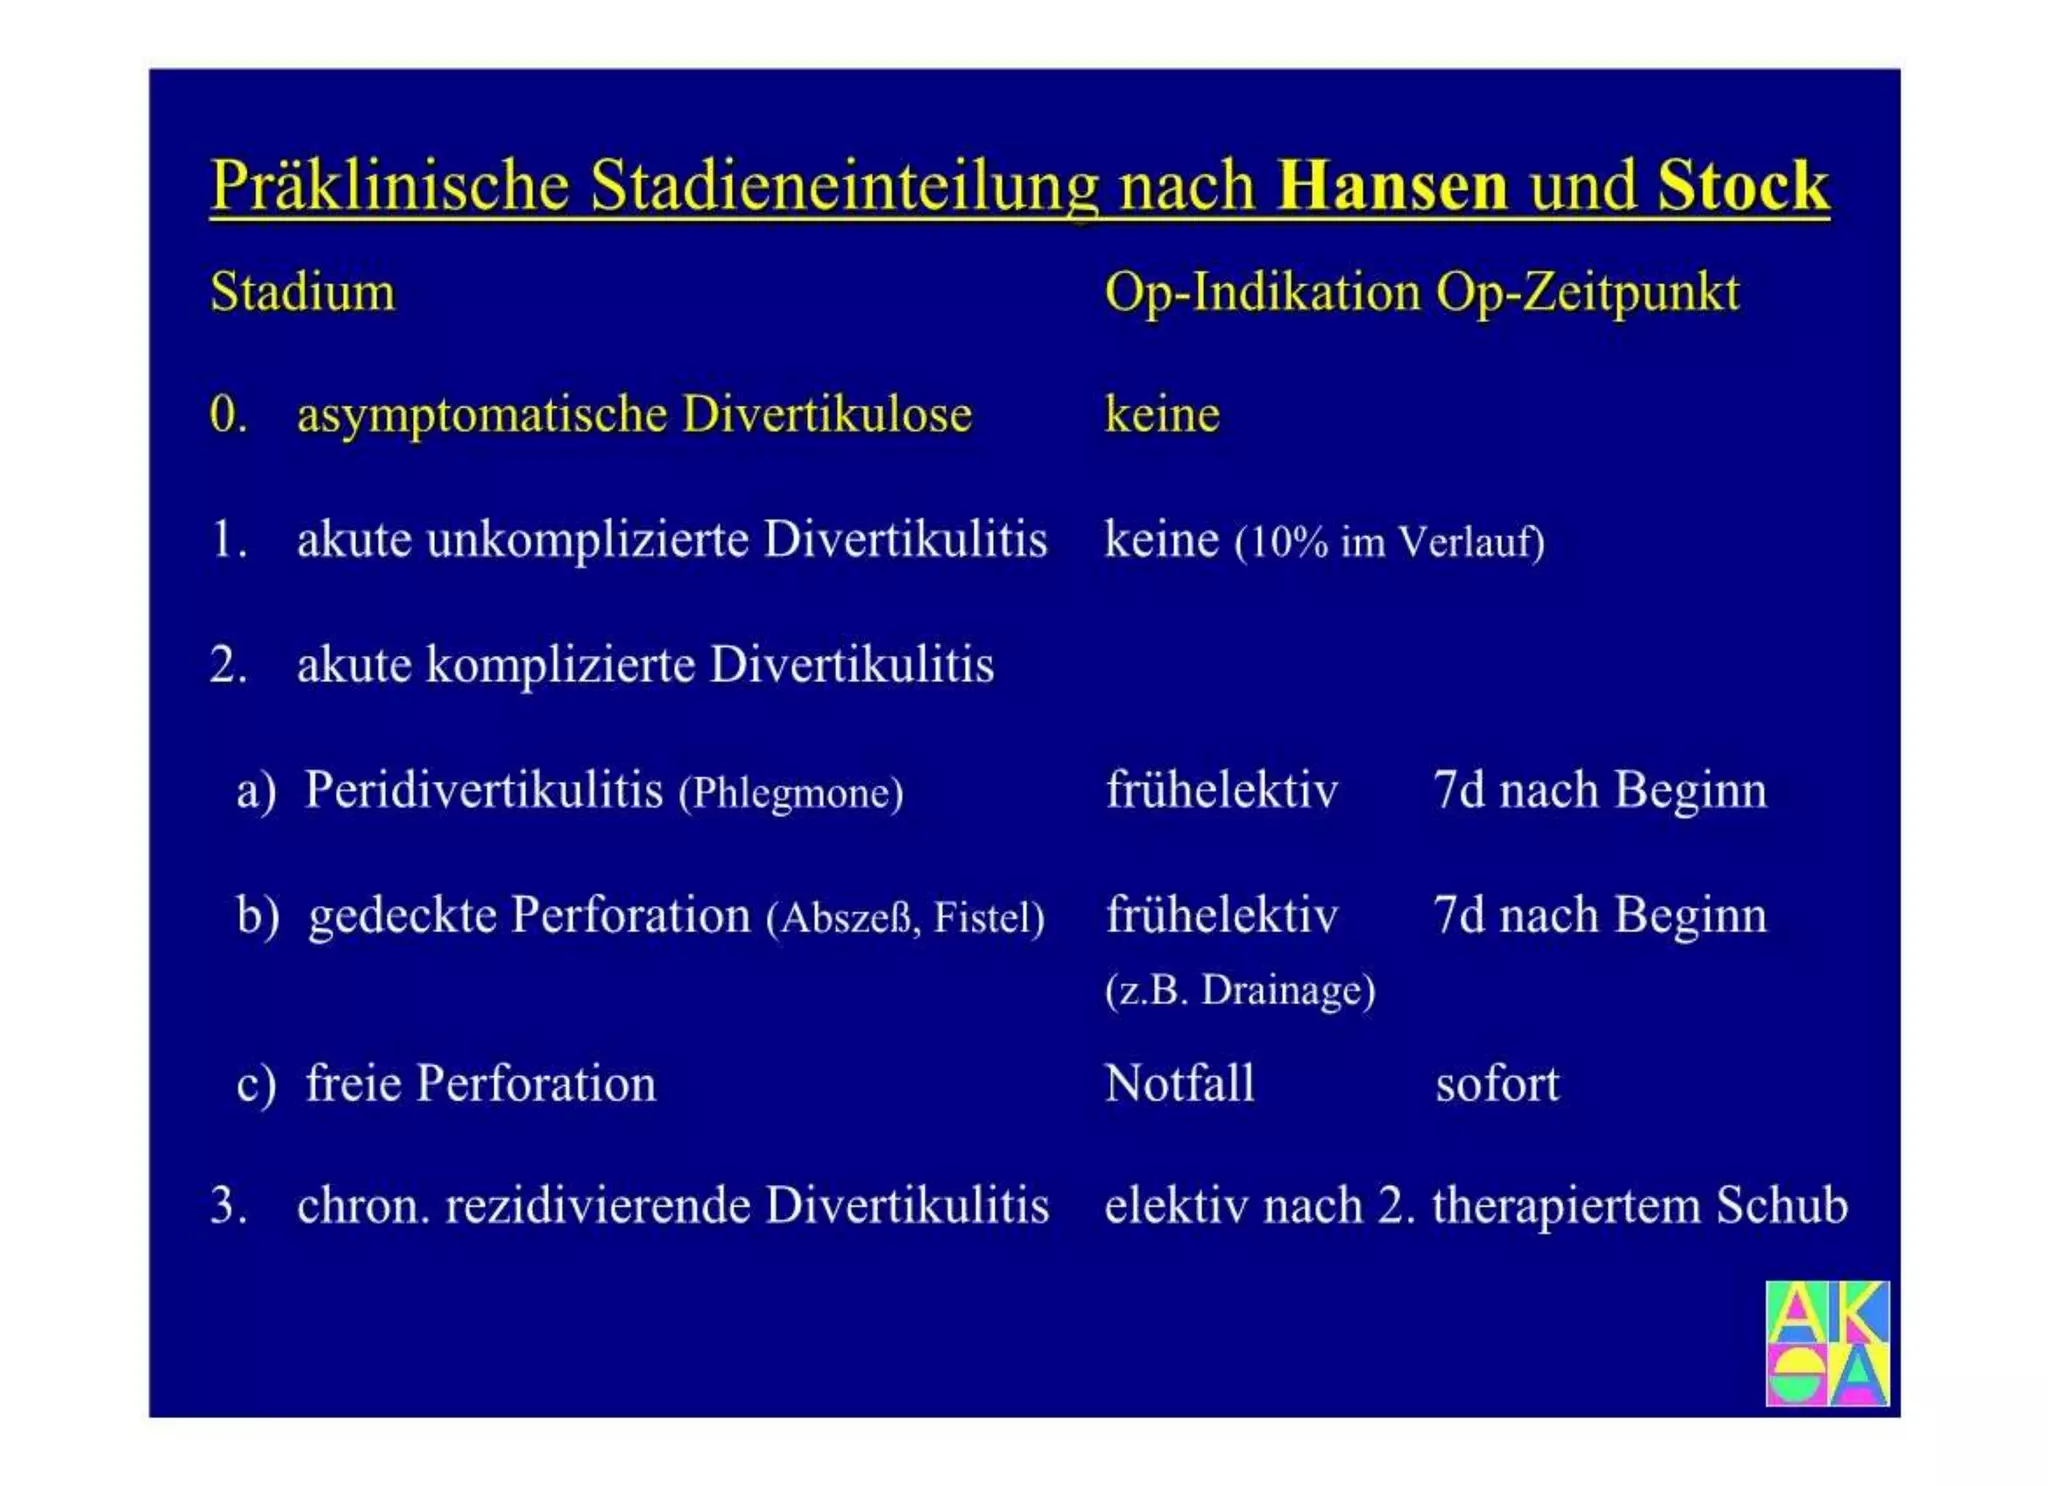

Chronische Enteropathie und Ileus, Dünndarm und Dickdarmdiagnostik, Mechanischer und paralytischer Ileus, Eingeklemmte Darmabschnitte, aufgereihter Bridenileus, und dazu Dickdarmileus, eingeklemmte Hernien, Weitergabeskript